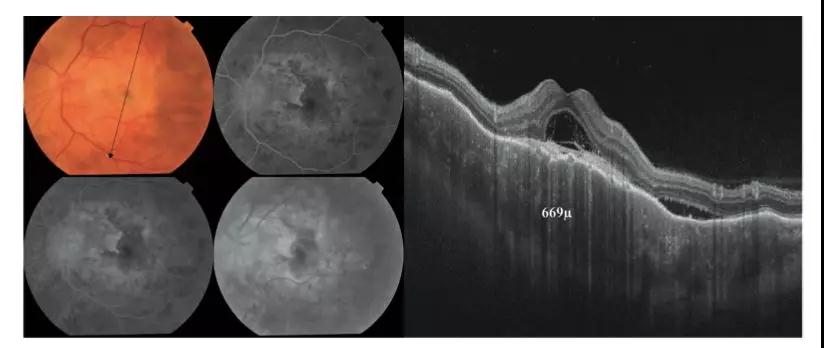

上图左:该患者左眼的彩色眼底照片和FFA。

除了VKH的急性期特征外,黄斑区还显示出视网膜下的黄绿色病变,表明FFA早期少量的渗漏,晚期染色则提示其主要为瘢痕成分。右图:径向扫描SS-OCT显示脉络膜增厚(669μm)。